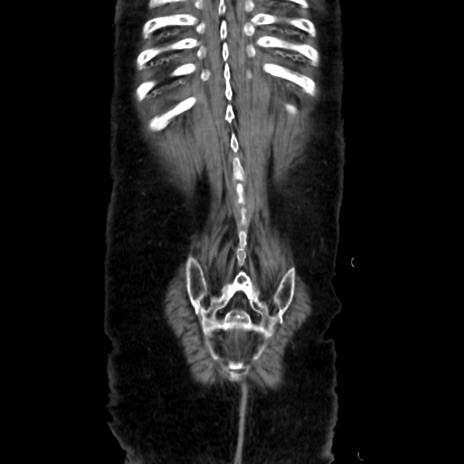

症例40(冠状断像)

【症例】90歳代女性

【主訴】腹痛・嘔吐

【現病歴】 食欲低下、嘔吐があり昨日他院受診。肺炎と診断され入院となる。入院後より腹部全体に圧痛あり。胃管留置され経過みていたが、症状持続するため、

当院転院となる。

【既往歴】胸椎圧迫骨折、胆石症

【身体所見】腹部:中央に激痛あり、圧痛あり、反跳痛不明

【データ】WBC 17100、CRP 18.82

矢状断像